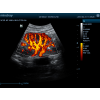

- Pulse Wave Doppler

- Pulse Wave Doppler